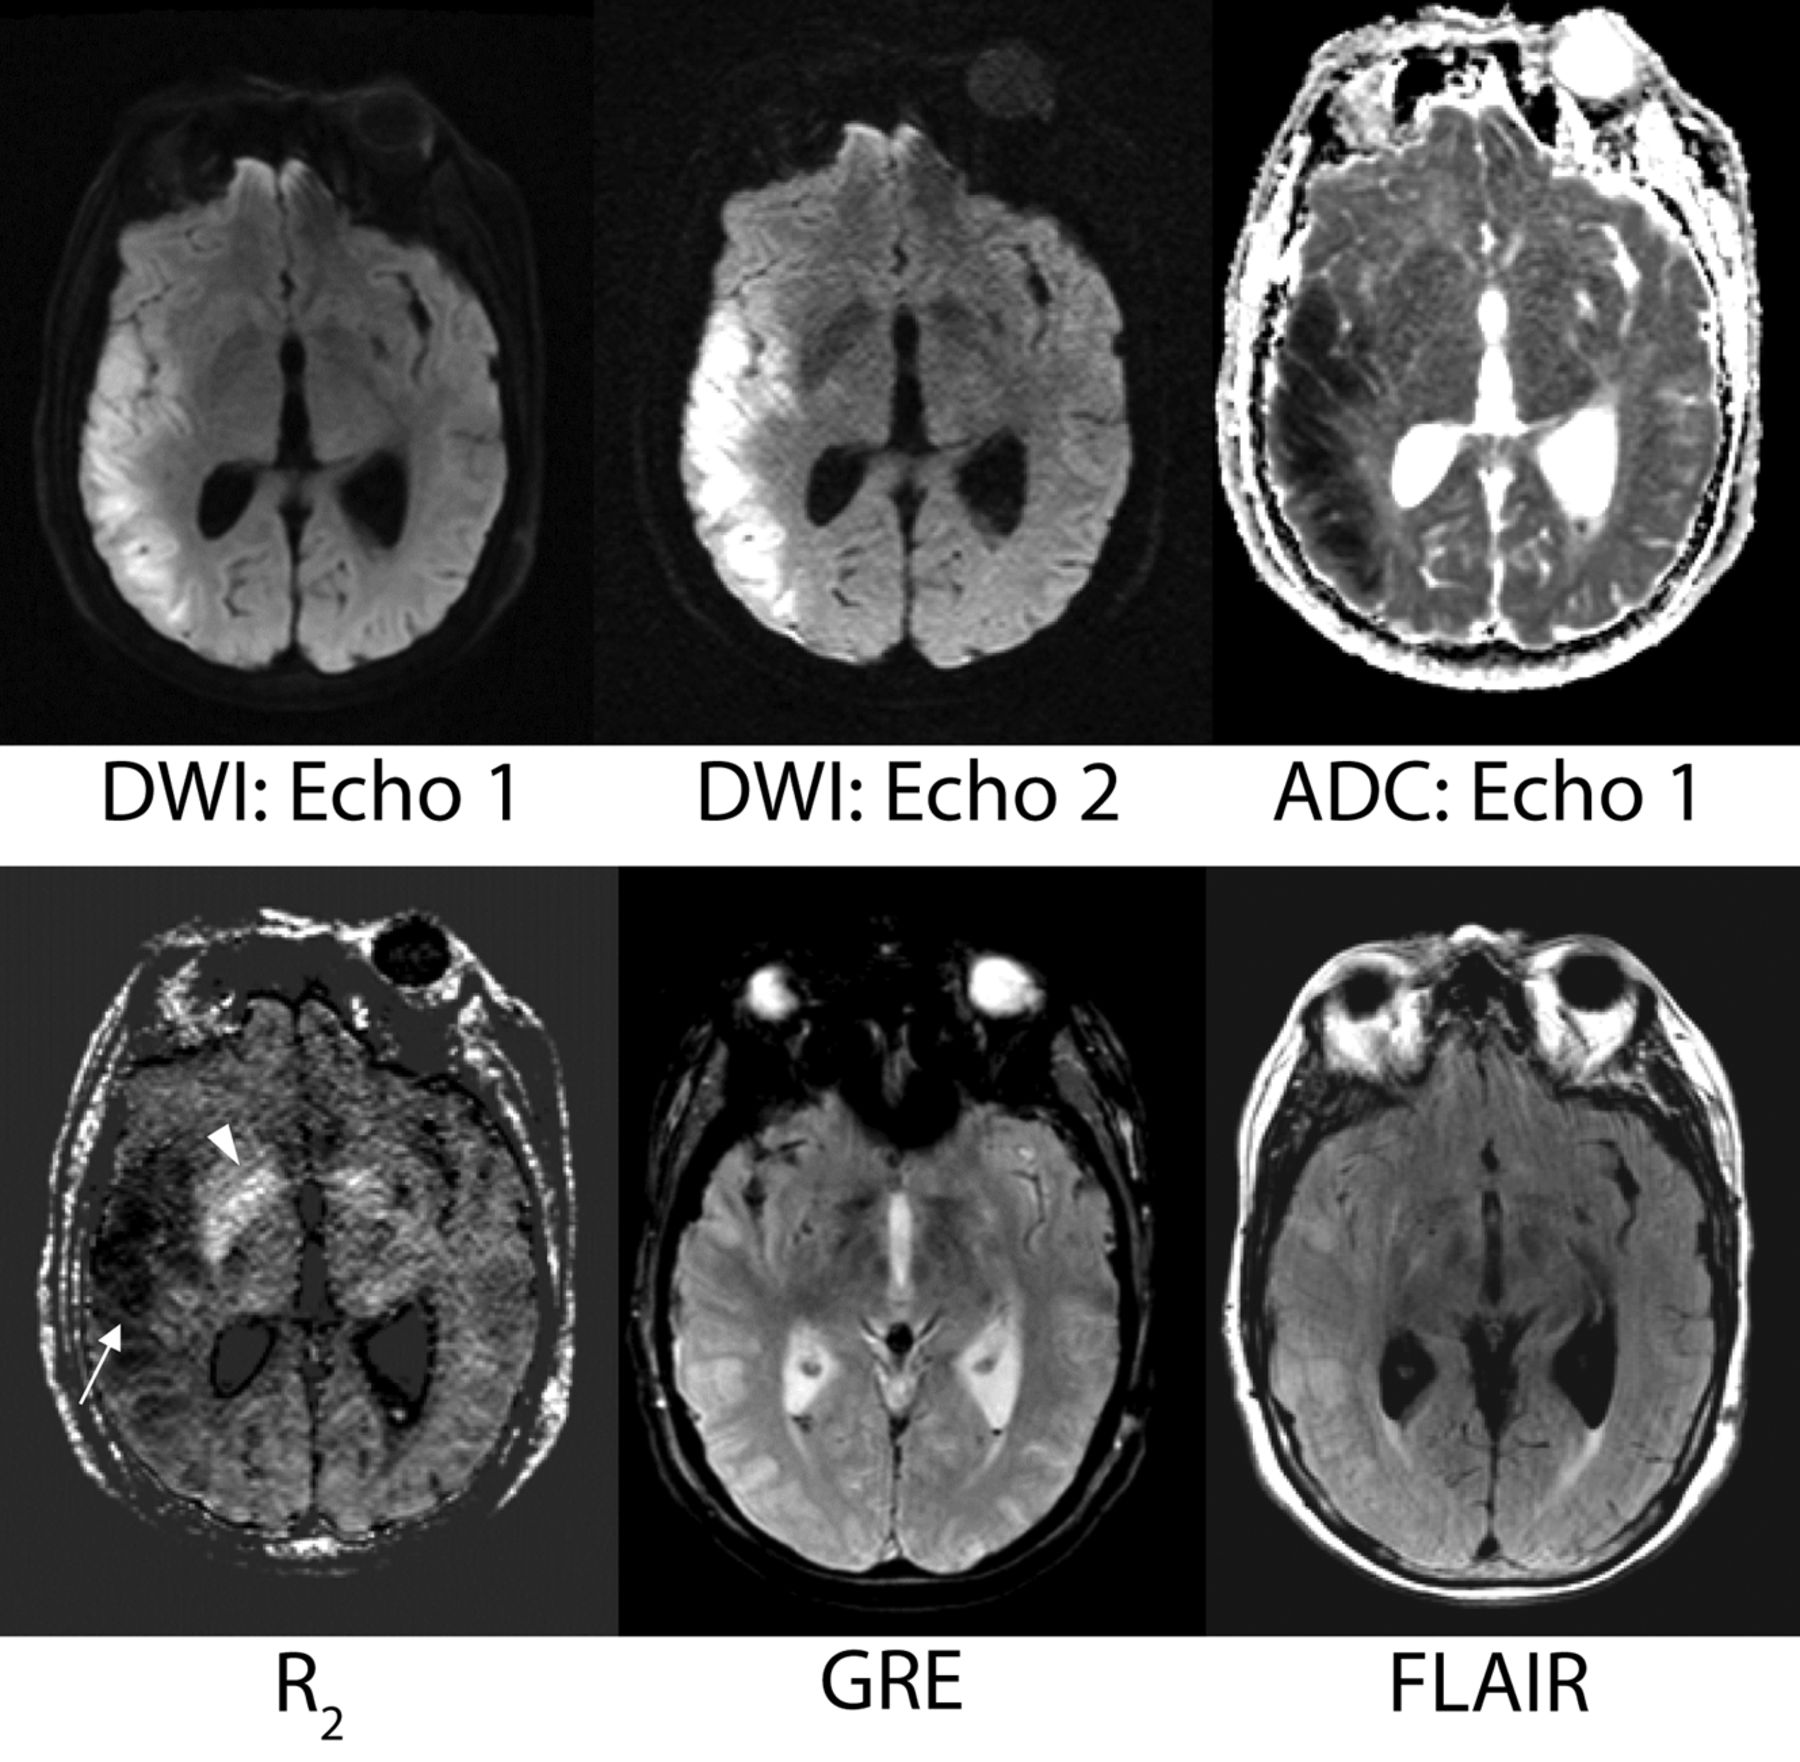

Figure 3 is representative of a case in which the routine product DWI sequence demonstrated lower diagnostic confidence compared with echoes 1 and 2.

Comparison of the vendor-supplied (product) DWI, echo 1, and echo 2 DWI acquired from the dual-echo sequence on 3 patients (from left to right). The ADC (calculated from echo 1) shows the presence of reduced diffusivity in each lesion (far right column). A, A 62-year-old female patient with stroke. B, A 49-year-old male patient with vasospasm and infarction post-aneurysm clipping. C, An 88-year-old woman presenting with strokelike symptoms. Note that the small infarct in the splenium of the corpus callosum present on the dual-echo DWIs was initially missed on the product DWI.

Figure 3 is representative of a case in which the routine product DWI sequence demonstrated lower diagnostic confidence, due to inferior image quality, compared with echoes 1 and 2. In this case, a small infarct present on the dual-echo DWI on Fig 3C was initially missed on the product DWI, a finding that could have prompted further clinical investigation for the source or altered risk for future stroke. Figures 4 and 5 show cases in which echo 2 demonstrated improved lesion conspicuity and diagnostic confidence compared with echo 1. Figure 5 also shows an example of a missed contralateral lesion that would have changed the clinical management of the patient because it raised the possibility of an embolic source of infarction. Note that many lesions detected on echo 2 could be seen retrospectively, either by a side-by-side comparison with echo 1 or the product DWI, or simply by scrolling through the images at a considerably slower rate than is performed in a typical clinical practice.